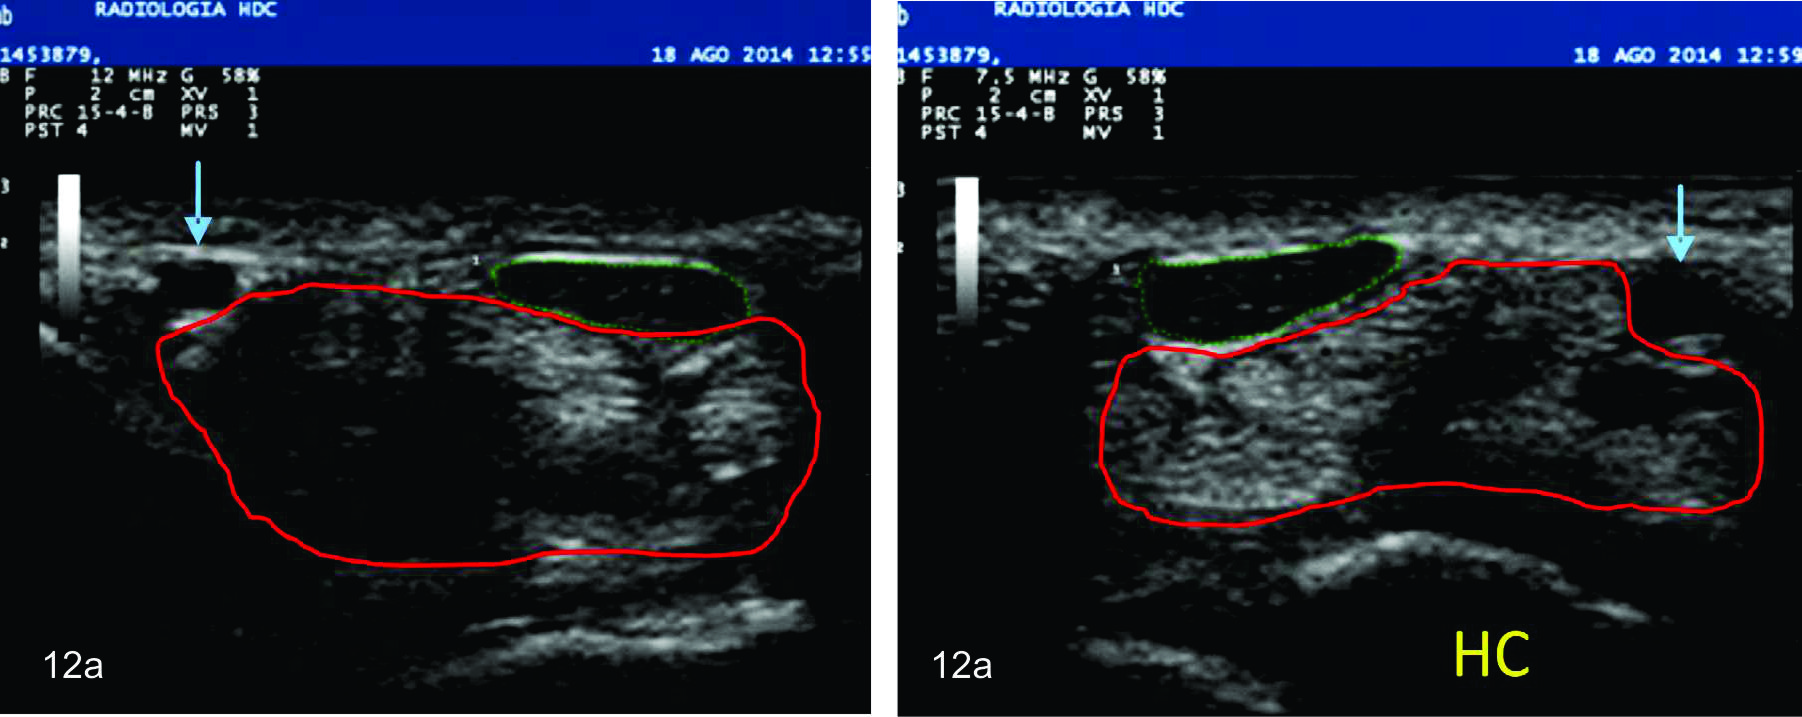

Figura 12 a

Síndrome del túnel carpiano bilateral

Se observa dos cortes comparativos bilaterales del nervio mediano (trazo verde) en su eje corto o transversal en la zona proximal del túnel. Se identifica en ambas imágenes un aumento del área esperada del nervio, el cual se encuentra hipoecogénico y ha perdido el patrón fascícular habitual. Trazo rojo- Tendones flexores, Flecha azul- Arteria cubital, HC- huesos del carpo.